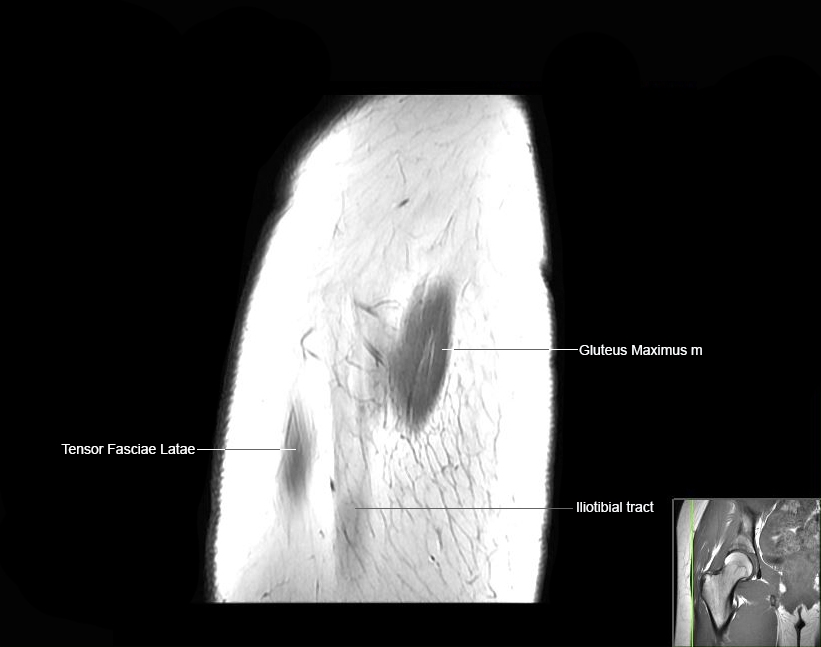

MRI Hip Anatomy

Scroll using the mouse wheel or the arrows